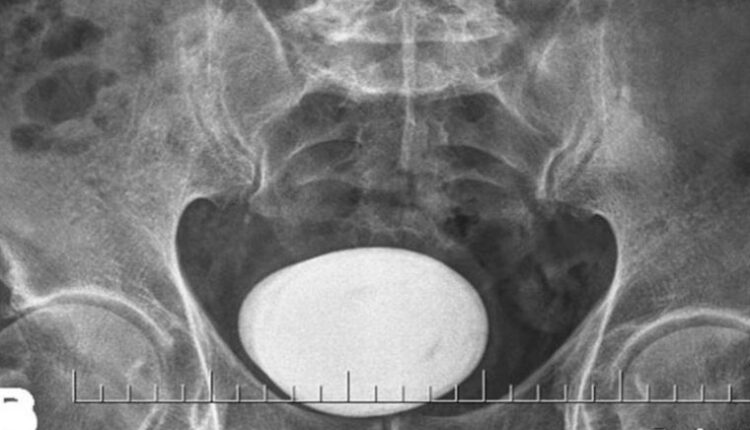

Mesanesinden patates büyüklüğünde taş çıktı, doktorları şaşırttı

Yapılan tetkik ve tahliller sonucunda hastanın mesanesinde çok büyük bir taş saptandı.

Literatürde bu boyda taş görülmesi çok nadir karşılanırken hastanın mesanesinden çıkan taş şaşkınlıkla karşılandı. Derhal ameliyata alınan hastanın mesanesindeki taş kapalı yöntemle çıkarılması mümkün olmadığından açık sistolitotomi ameliyatı yapıldı.

Herkesi şaşkına çeviren büyük bir patates yumrusu şeklindeki taş başarılı şekilde alındı.